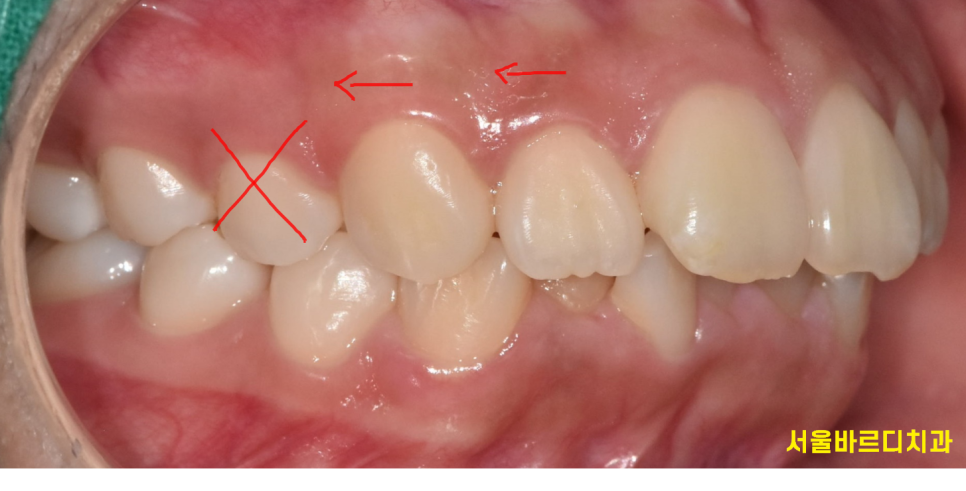

공간이 부족하여 제 위치를 벗어나 올라오는 덧니가 있을 수도 있고요~

2)돌출입 개선

흔히 입툭튀라고 하죠.

입이 툭 튀어나온 돌출입의 경우

발치를 통해 치아를 뒤로 이동시켜 입 모양을 개선할수 있습니다.

물론 발치를 안하는 쪽으로 교정을 해볼 수도 있지만

이럴 경우 원하는 만큼의 돌출입 개선이 안될수 있습니다.

돌출입의 경우 심미적인 목적으로 교정을 많이 하시기 때문에

이 안뽑고 교정은 치료가 끝나고 불만족스러울 수 있습니다!!